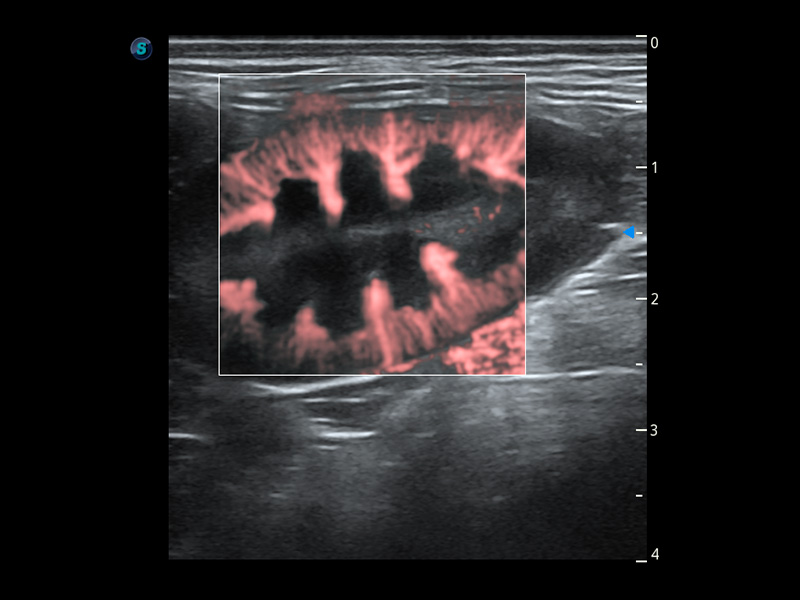

ProPet 60 作为一款高端台式动物超声设备,为动物医生的日常诊断提供了一系列贴合动物临床需求、解决临床实际问题的高级成像功能。凭借全系列高清探头,满足医生对腹部、心脏、生殖、浅表、肌骨等成像的所有需求,切实帮助您提升检查效率,提高诊断信心。

动物是人类最亲密的朋友和最值得信赖的伙伴。银河优越会也一直致力于探索动物专用的超声影像解决方案。 全新推出的ProPet系列,是银河优越会在动物超声影像智能化、专业化、精准化的一次跨越式革新。动物不能用言语来表述自己的不适,通过超声影像,ProPet系列搭建了动物医生与不同物种沟通的“桥梁”,为动物医生注入了“治愈之力”。